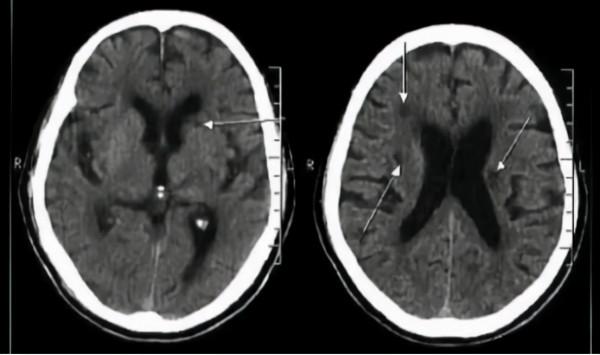

(腔隙性腦梗塞圖)

腔隙性腦梗塞屬於小動脈閉塞性的腦梗死,多存在於腦部的深穿支動脈。在血管壁發生病變後會出現血管閉塞的現象,而閉塞的血管會因為缺血而梗死,梗死後則會呈現出微小腔隙的狀態。通常腔隙的形狀大小都是不規則的。而這些不規則的微小腔隙就被稱為腔隙性腦梗塞。

腔隙性腦梗塞的發病部位通常體現在尾狀核、丘腦、內囊等,常見於五十歲以上的老年人。而因這類腦梗塞大多是由糖尿病、高血脂等疾病發展而來的,所以在中年階段也有很多病患。

而腔梗只是大腦深處的小動脈有閉塞現象產生。之後便會形成幾毫米區域的梗塞,梗塞區域的腦組織最終會被形成液體的狀態,從而被身體吸收,吸收過後的區域就會變成一個個細小的間隙。

還有一種特殊情況,人的身體在逐漸衰老的同時,大腦中的血管也會逐漸的萎縮,萎縮過後的血管也會形成一個個小小的間隙。這些間隙會被醫學影像檢測出來,而這種間隙不能成為疾病。